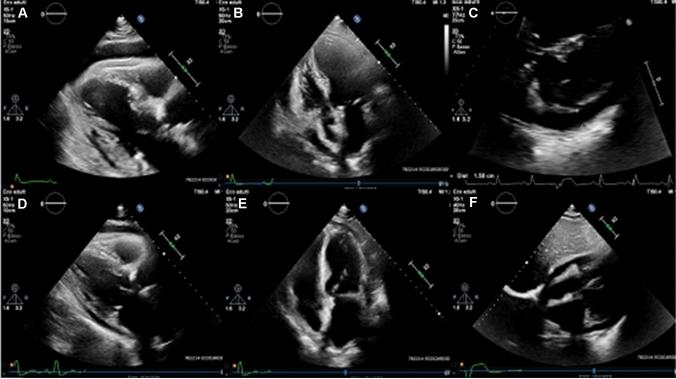

早期使用阿那白滞素可改善金黄色葡萄球菌败血症所致的急性心包炎并预防心包填塞。

Early introduction of anakinra improves acute pericarditis and prevents tamponade in Staphylococcal sepsis.

The clinical response to anakinra observed by this patient concurrently treated with antibiotics indirectly confirms the potentially pathogenic role of IL-1 in maintaining the pericardial disease and shows how IL-1 blockade might allow avoiding the pericardiocentesis procedure. The report supports the hypothesis that anakinra is an effective and safe tool in the early treatment of acute pericarditis of presumed bacterial origin nonresponding to targeted antibiotic therapy.

摘要